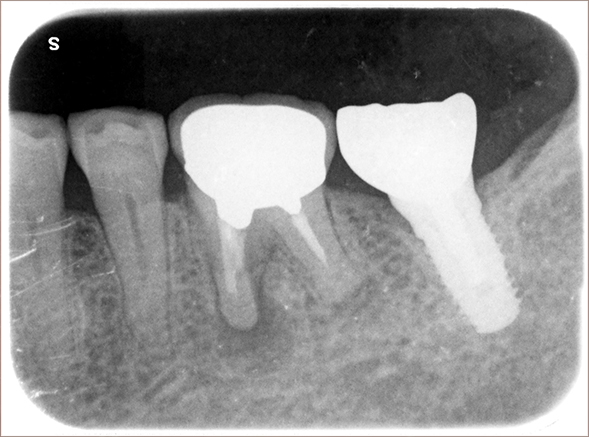

2008年8月27日撮影

インプラント埋入部の骨レベルは埋入時と変わらず、患者様ご自身のメンテナンスも良好で、経過は非常に良く、満足されています。